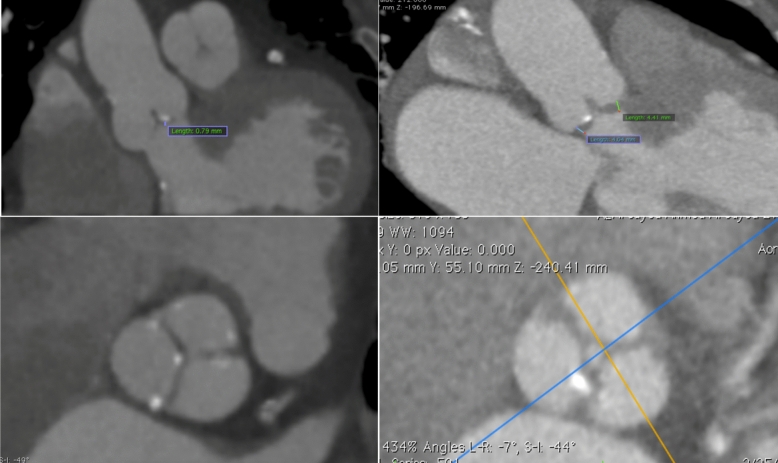

Abstract Image